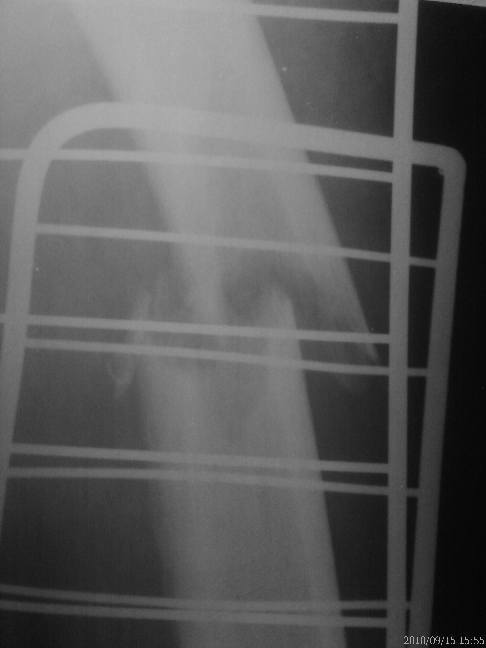

2 недели назад пациент поскользнулся, сломал бедро. 4 месяца назад проведена

нефроэктомия по поводу опухоли почки. На рг патологический перелом бедра. От

наложения гипсовой повязки отказывается настаивает на оперативном лечении.

Интрамедуллярный остеосинтез блокирующими гвоздями нет возможности провести.

Планируем остеосинтез пластиной LCP винтами.

Проводить резекцию кости? Какой обьем резекции?